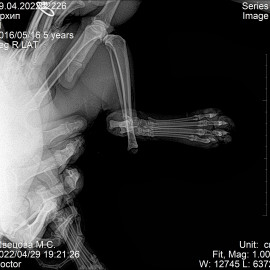

Наш пациент, кот, по кличке Архип.

Обратились к нам после автотравмы с жалобами на отсутствие опороспособности на правую заднюю лапу.

Было проведено рентгенологическое исследование.

Поставлен диагноз: перелом правой голени, вывих правого голеностопного сустава. Была проведена операция: остеосинтез правой голени, остеосинтез правого голеностопного сустава.

Снимок 1-2 до операции.